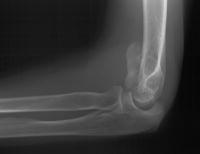

She began immediate protected motion and discontinued splint use at two weeks, despite recommendations to the contrary. These films are two months postop:

Lateral column not yet fully consolidated on Xray, but clinically healed.

Flexion:

Extension: